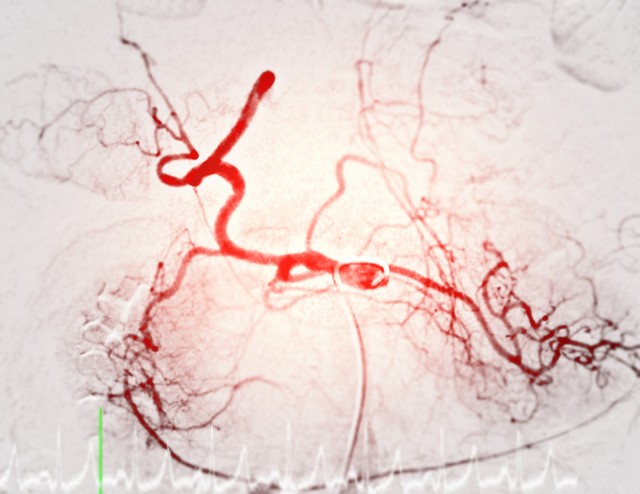

Mi az arteriográfia és mit mutat ki?

Az arteriográfia egy speciális orvosi képalkotó vizsgálat, amelyet az artériák állapotának felmérésére használnak. Ez a módszer kontrasztanyagos röntgenvizsgálaton alapul, és lehetővé teszi az érrendszer pontos megjelenítését. Az arteriográfiát gyakran alkalmazzák szív- és érrendszeri betegségek diagnosztizálására, érszűkületek vagy elzáródások kimutatására, valamint a stroke és a szívinfarktus kockázatának felmérésére.